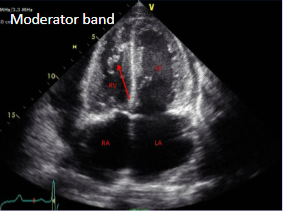

Moderator band

Muscular structure located in the right ventricle of the heart.

Can be mistaken for a right heart thrombus.

<p>Muscular structure located in the right ventricle of the heart.</p><p>Can be mistaken for a right heart thrombus.</p>

61